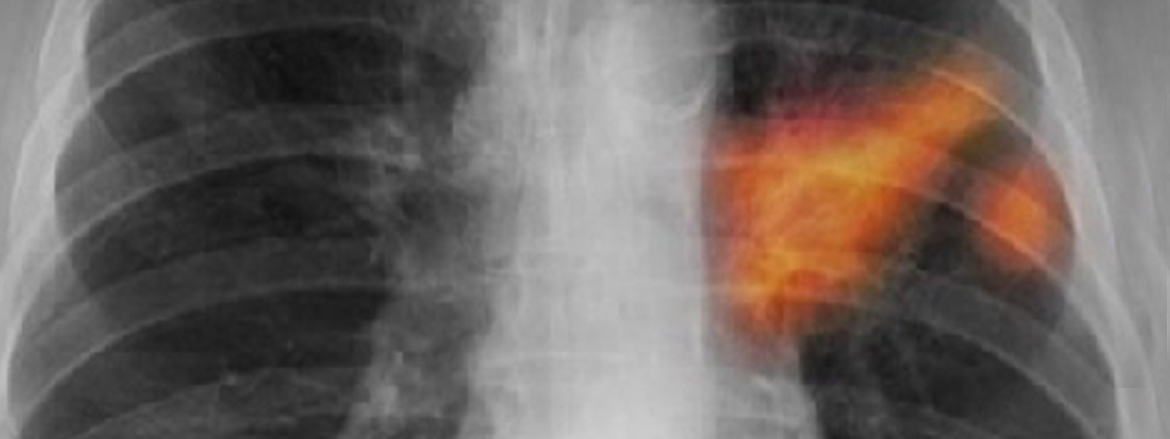

Halk içinde dıyk-ı nefes dimekle meşhurdur. Bu bir marazdır ki alât-ı nefesde olur. Tiz tiz solur ve nefesini gücle alur ve yorgun âdem gibi solur. Bu illet eğer pîrlerde olursa bu marazdan halas olmak olmaz.